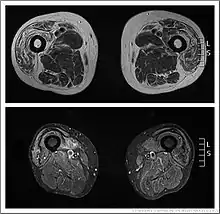

| Bilateral medial forearm and quadriceps wasting of inclusion body myositis (rimmed vacuole within a muscle fibre histopathologically ) | |